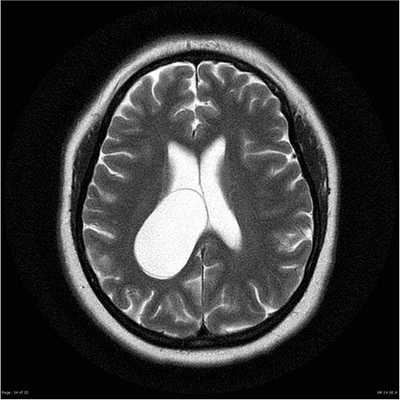

Магнитно-резонансная томография мозговой кисты

Небольшая киста головного мозга не представляет опасности при локализации вне функциональных центров. Морфологически образование имеет вид полости с жидким внутренним содержимым. Пузырь может находиться внутри белого или серого вещества всю жизнь. Если образуется после травмы, увеличивается в размерах, требуется динамический контроль полости.

Аутоиммунные кисты постепенно прогрессируют. Динамическое выполнение МРТ помогает отслеживать состояние пузыря. При растущем образовании потребуется оперативное лечение. Абсолютная норма на фоне аутоиммунного повреждения мозговой ткани требует повторной магнитно-резонансной томографии не позднее 1 года.